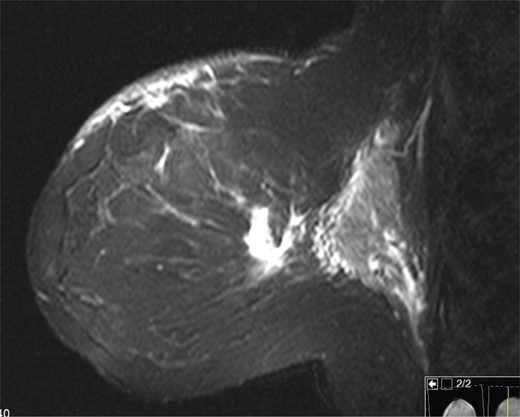

The patient is a 47-year-old Polish premenopausal female who presented with complaints of a non-tender palpable left breast mass for 4 months at an outside institution. She underwent a diagnostic mammogram and ultrasound that reported a 2-cm irregular, hypoechoic mass at 12 o'clock. The mass had indistinct borders on ultrasound (Figs. 1,2). Bilateral breast MRI revealed no disease in either axilla or the right breast. There was a 2.2-cm enhancing mass in the left breast at 12:00 that was consistent with the patient's biopsy-proven malignancy (Fig. 3). Upon examination in the Breast Surgery clinic, she underwent a core needle biopsy, which revealed a poorly differentiated triple-negative invasive ductal carcinoma (Fig. 4).

Left breast on MRI. There was a 2.2 cm enhancing mass in the left breast at 12:00 that was consistent with the patient's biopsy-proven malignancy.